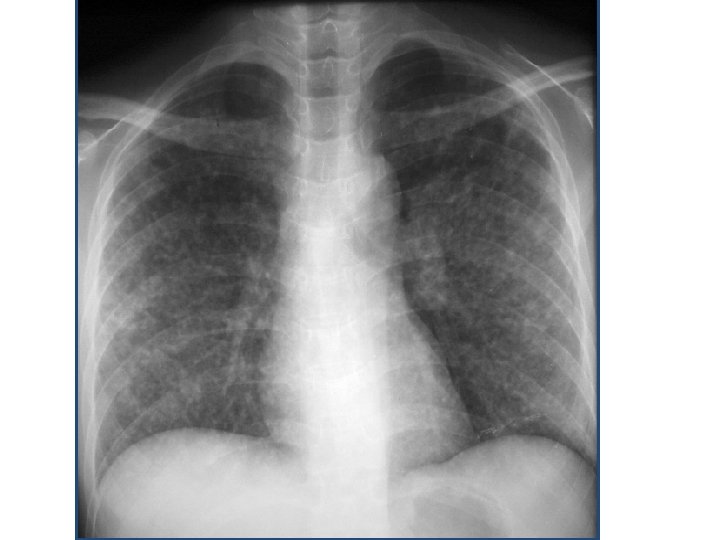

Définition : exclusivement radiologique. • Classiquement présence au niveau des plages pulmonaires d’opacités micronodulaires de taille d’un grain de mil (1, 5 à 3 mm de Ø) diffuses ou localisées. • les aspects moins typiques : des images réticulaires et réticulo-nodulaires.

Diagnostic positif : A- Circonstances de découverte : • Examen radiologique systématique. • A la suite d’une symptomatologie respiratoire. • Au cours de l’évolution d’une maladie générale. B- Radiographie de thorax : • La radiographie permet de reconnaitre l’image miliaire par la présence d’un semis d’opacités de 1, 5 à 3 mm de Ø de densité et de répartition variable on distingue 2 types :

a- miliaires pulmonaires typiques : micronodules caractérisées par : contours arrondies et séparés les unes des autres. dimensions égales. Répartition égales dans les 2 champs pulmonaires avec imprégnation plus importante dans les régions moyenne par rapport aux bases et aux sommets. • Présence possible d’un aspect en maille de filet avec des granulations constituant l’aspect réticulo-nodulaire. • •